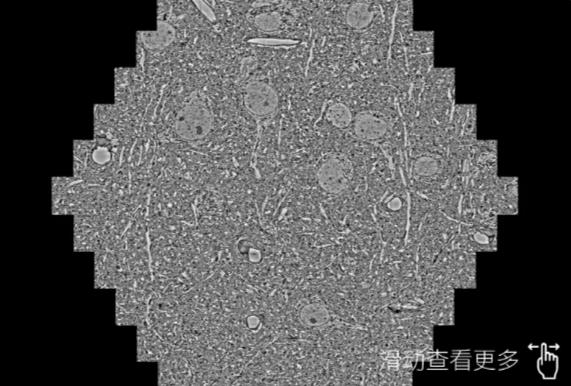

鼠脑切片。左图使用五指山蔡司五指山扫描电镜MultiSEM706对165μmx143pm面积区域成像,耗时仅需1.5秒。右图为鼠脑切片中30μm区域放大效果。样品由芝加哥大学B.Kasthuri提供。

使用蔡司高速五指山扫描电镜MultiSEM对1mm²人脑皮层组织进行高分辨成像,并对其中的各种细胞结构进行三维重构分析。左图展示了2x3mm²组织平面中锥体神经元的三维重构效果。右图显示了局部体积神经元三维重构。图像由哈佛大学chtman实验室提供,渲染图由D. Berger 制作。